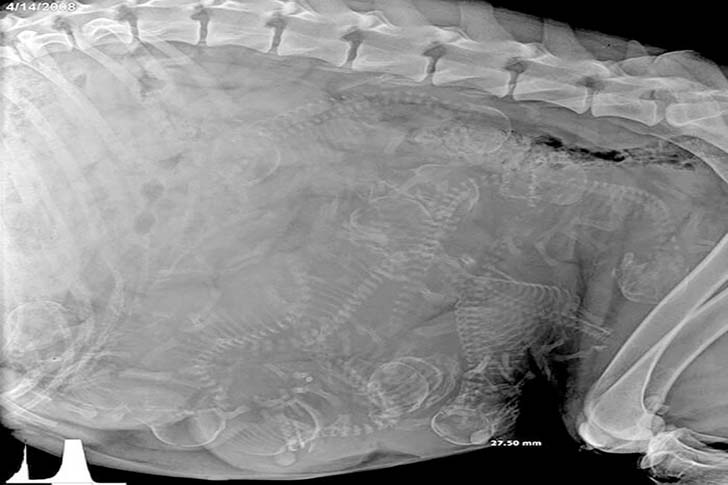

この写真にタイトルが付いていないとして、一つの大きな体の中に無数の小さな骨があるという奇妙な状態を説明するために、あなたの頭の中では様々な可能性が広がっているかもしれません。しかし、その背景を理解すると、実はとても驚くべきことなのです。狭い場所にたくさんの骨が密集していて、これが “自然” であることは衝撃的です。なんとこれからたくさんの子犬が産まれてくるのです!

人間の妊娠中の超音波検査は見慣れた光景ですが、妊娠中のワンちゃんののレントゲン写真には驚かされるばかりです。